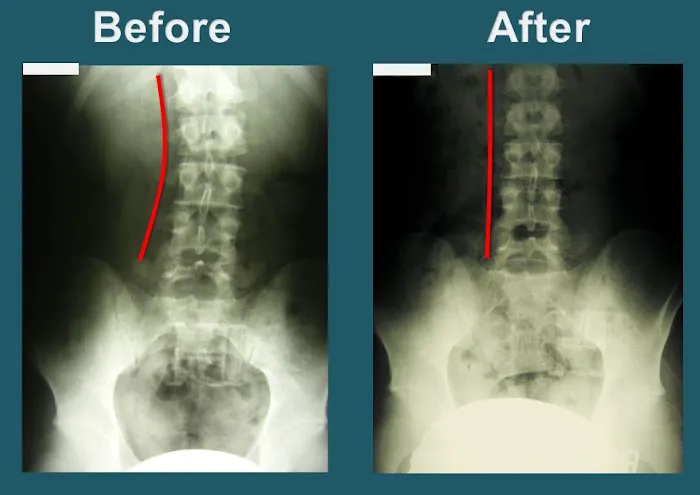

Precision Spinal Adjustments: Dr. Park is highly skilled in performing "precise" adjustments to correct spinal misalignments. Patients consistently report feeling "improvement after each visit," indicating the effectiveness and accuracy of his techniques in restoring proper spinal function.

Treatment for Serious Back Injuries: The clinic has a proven track record of helping patients recover from significant back injuries. Patients have experienced remarkable recovery, being able to return to their "normal life" after just a few weeks of treatment for serious conditions.

Proven Effectiveness for Serious Injuries: The clinic has a remarkable track record of helping patients recover from severe conditions. Testimonials include individuals who "walked into the clinic with a serious back injury and could barely move" and were able to "return to my normal life" after just two weeks. Similarly, recovery from a "shoulder dislocation and a misaligned spine due to an accident" highlights their capability in handling complex trauma.

Consistent and Noticeable Improvement: Patients consistently report feeling "improvement after each visit." This consistent progress is a testament to the effectiveness of Dr. Park's precise adjustments and tailored care, building momentum towards full recovery.

Secondly, the remarkable speed and effectiveness of recovery at Yonsei Chiropractic Clinic are compelling. The testimony of someone returning to "normal life" after only "two weeks of treatment" for a "serious back injury" speaks volumes about the clinic's ability to provide "real relief" and restore function efficiently. For busy Californians, minimizing downtime and quickly regaining mobility are invaluable, and Yonsei Chiropractic consistently delivers on this front.

Lastly, the consistent "improvement after each visit" reported by patients underscores the high quality and effectiveness of the adjustments. The significant relief experienced, such as a shoulder and spine feeling "so much better" after an accident, demonstrates the clinic's capacity to handle challenging cases with exceptional results. The convenient location on Wilshire Boulevard in Los Angeles further enhances its appeal, making this top-tier chiropractic care easily accessible for many locals. For anyone in California seeking a truly professional, effective, and genuinely caring chiropractor to help them recover from injuries or improve their spinal health, Yonsei Chiropractic Clinic is an outstanding choice, deserving "Five stars all the way!"

Apr 16, 2025 · Leo MiguelExceptional Chiropractic Care – Dr. Park is the Best!I had a shoulder dislocation and a misaligned spine due to an accident, and Dr. Park at Yonsei Chiropractic truly helped me recover. From the beginning, he was very thorough, taking an X-ray before starting any treatment to pinpoint exactly what needed to be fixed. He explained everything clearly, which made me feel confident and reassured throughout the process.The adjustments were precise, and I could feel the improvement after each visit. Now, my shoulder and spine feel so much better. The clinic is clean, well-organized, and has a welcoming atmosphere. The staff is also very friendly and professional.If you’re looking for a chiropractor who is skilled, caring, and detail-oriented, I highly recommend Dr. Park. Five stars all the way!